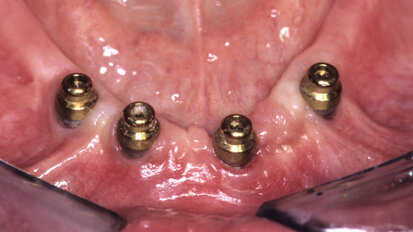

Treatment options for the edentulous arch

Historically, when a patient’s dental condition reached a state of total tooth loss, treatment was limited to a complete denture with no hope of ...